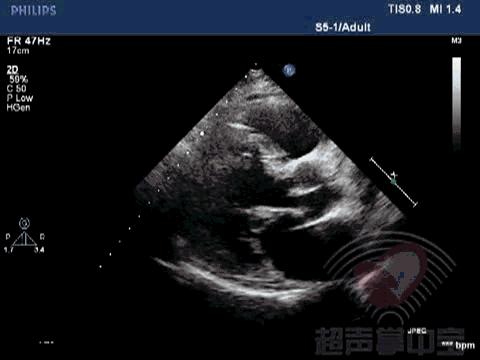

二尖瓣充血性囊肿,二尖瓣血性囊肿是什么意思 动态图3:左室长轴切面观察该囊状物质软,有形变,随二尖瓣运动而摆动